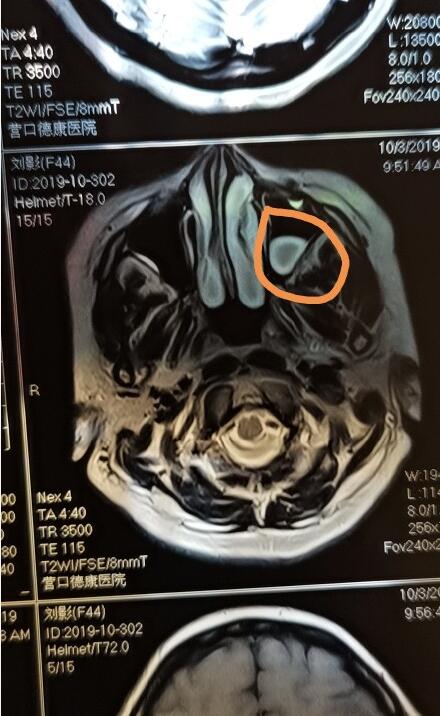

脑垂体瘤的面相是什么样的?

脑垂体瘤易发于青壮年,男性多于女性,大部分都是良性,但它带来的危害却是很大的。

他会影响内分泌腺,扰乱激素的产生,导致患者生育能力,情绪管控、学习能力出现状况,还会导致骨骼,软组织的异常发育。

巨人症就是脑垂体瘤比较常见的病征表象,但并不是所有的脑垂体瘤患者身高都会疯长,有的患者得病后身高会停滞不长,比常人矮小。

如果有人发现短期内的自己明显变丑,如鼻子大,脸变长,嘴唇变凸变厚,脸部轮廓粗狂,皮肤粗糙,手指,脚掌变粗变厚,那就要警惕脑垂体瘤。

手术后面容还能恢复吗?

目前脑垂体瘤都是采用经鼻蝶微创手术,但是手术毕竟是在颅内,是存在一定风险的,必须权衡利弊谨慎考虑。

手术后患者的各种激素会恢复到正常水平,但对面容和肢体造成的变化却是不好恢复的,或留下些后遗症,骨头长长了不可能在缩回去,但增生的软组织是可以慢慢恢复的。总之这个病最好早发现早治疗恢复程度越好。 |